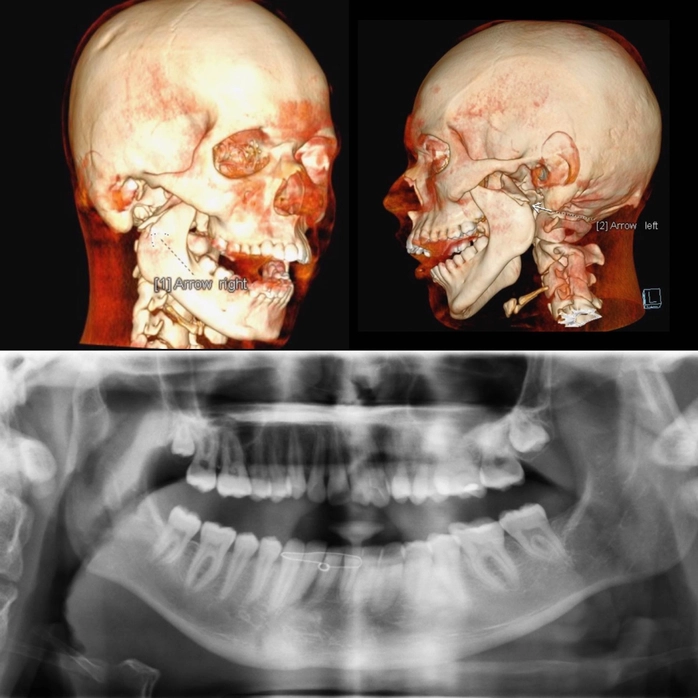

The condition of the jaw fracture can be simple or complex. For closed fractures with little displacement, or fractures on one side of the jaw, the cost will be lower compared to comminuted fractures (multiple pieces), open fractures, or those accompanied by damage to soft tissue, nerves, or teeth. The higher the severity, the longer the surgical time, the more materials required, and the post-operative care time increases accordingly.

Additionally, the application of support technologies such as 3D CT scanning and digital simulation can also increase the total jaw surgery cost.